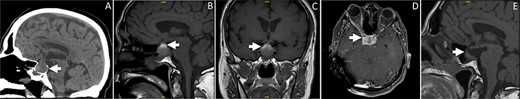

Computed tomography (CT) scan revealed widening of the sella turcica with an isodense soft tissue lesion in the pituitary gland (Fig. 1A). Magnetic resonance imaging (MRI) demonstrated a pituitary adenoma with acute hemorrhage causing right-sided mild mass effect on the cavernous sinus (Fig. 1B–D).

(A) Sagittal brain CT showing an isodense lesion in the pituitary gland associated with widening of the sella turcica. The lesion is causing a slight displacement of the pituitary stalk and optic chiam. (B–C) Sagittal and coronal sections of T1-weighted brain MRI without contrast. The MR images are demonstrating heterogneous signal of the pituitary lesion. The lesion is mainly hyperintense on T1-weighted images, indicating acute to subacute hemorrhage. The lesion is involving the sella and suprasellar region. (D) Axial T1-weighted brain MRI post contrast demonstrating enhancement of the pituitary lesion. (E) Sagittal MRI of the sella showing marked interval reduction in the size of the hemorrhagic cystic pituitary lesion. The small residual is measuring 1.1 × 0.5 cm. Interval resolution of the mass effect on the optic chiasm is noted.